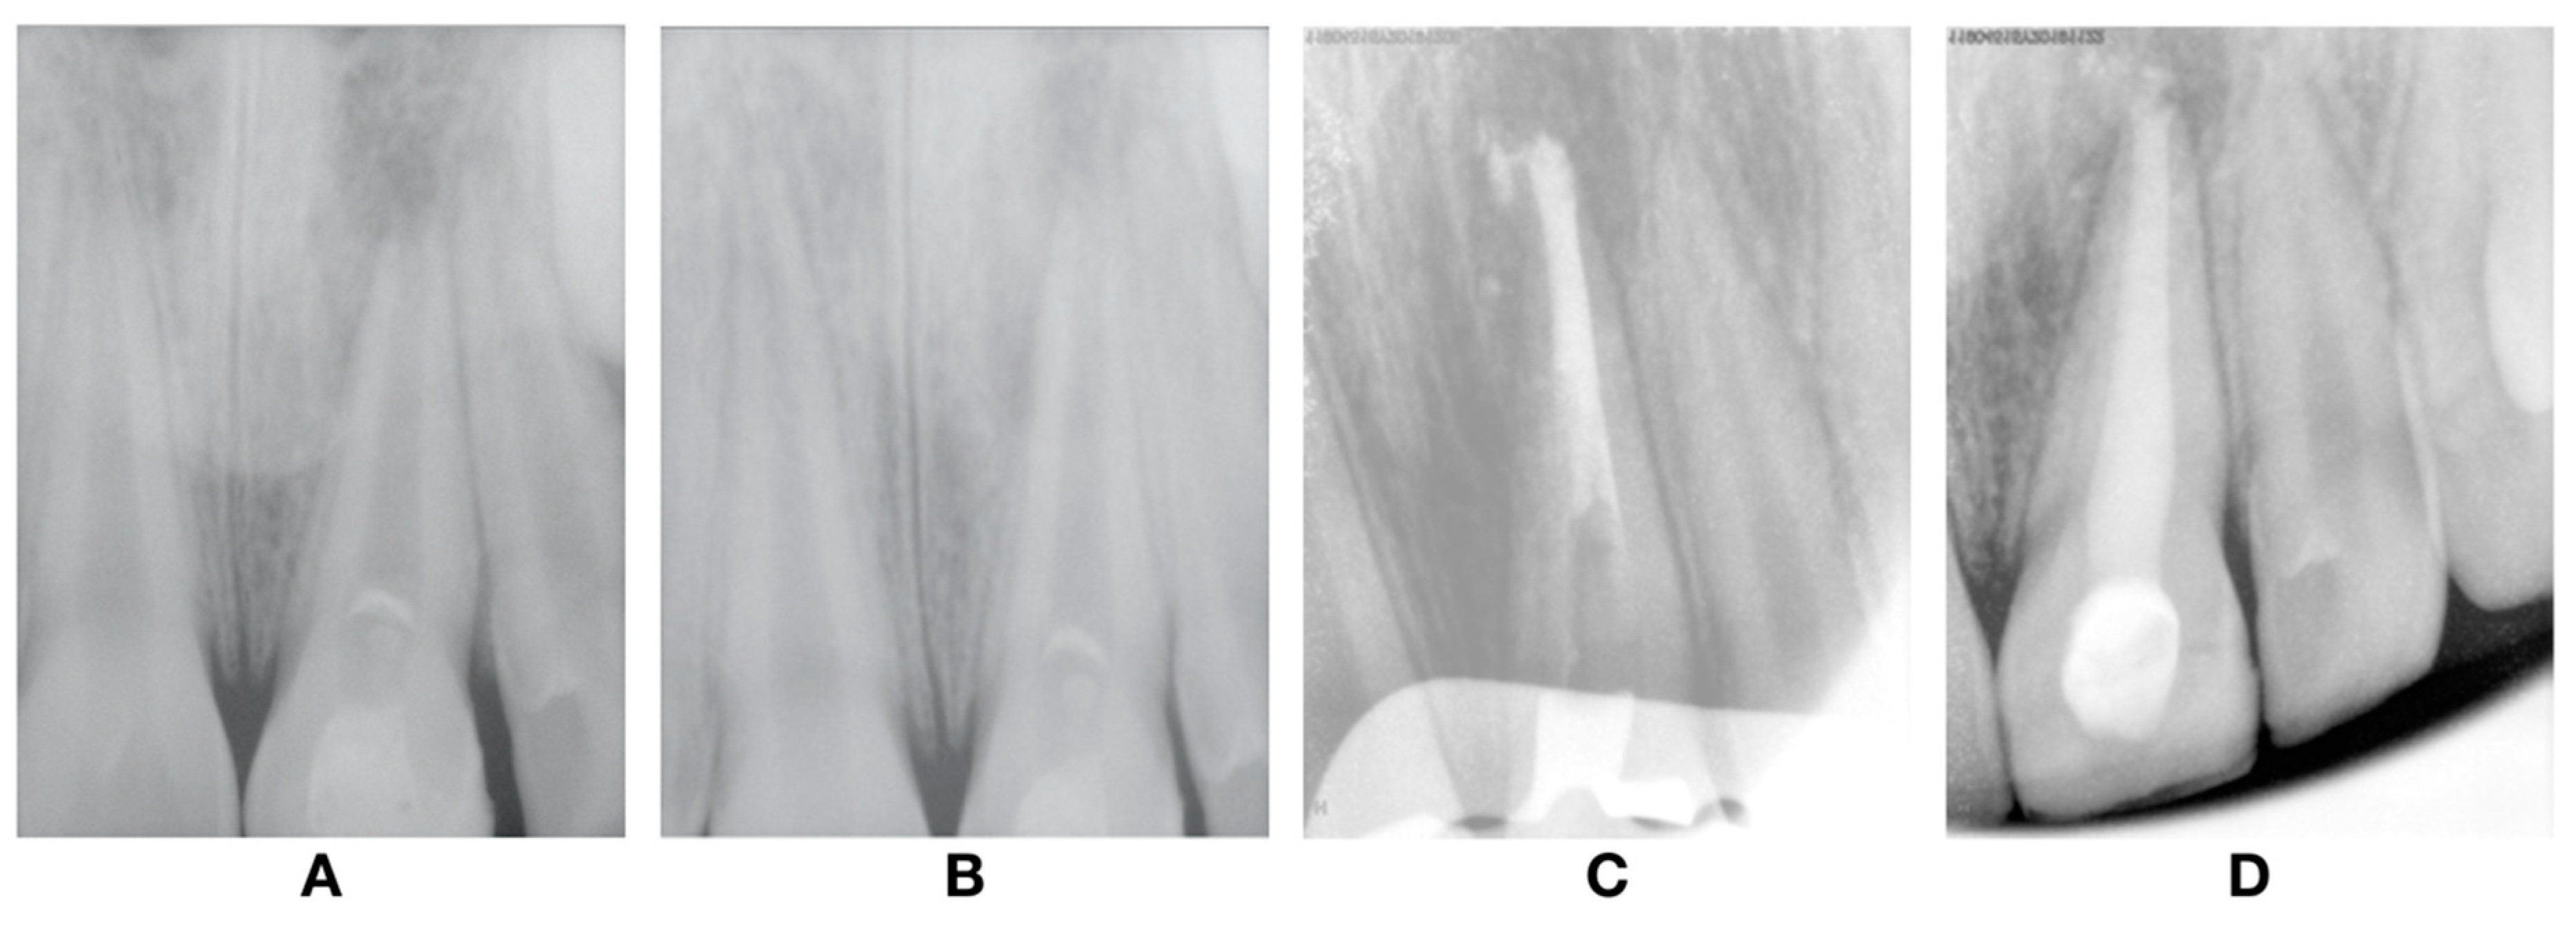

At one-year follow-up, clinical examination revealed no signs or symptoms of pulp injury and the soft tissues were healthy. Radiographic examination revealed no signs of dentine wall thickening or continuous root development (Figure 5A). In the two-year follow-up, the radiograph revealed evidence that there was no sign of root development and apical closure as well as dentine wall thickening (Figure 5B). Thereby, and taking the radiographic images in the last two-year findings into account, we concluded that the revascularization failed, and an alternative endodontic treatment had to be accomplished. At this stage, the treatment options presented were: (1) new attempt of the REP; (2) apexification with MTA; or (3) apexification with the Ca(OH)2 procedure. The apexification with MTA was the elected treatment and was performed over two visits.

Figure 5.

Follow-up radiographs after revascularization. (A) 1-year follow-up; (B) 4-year follow-up; and after (C) plug MTA; and (D) root canal obturation.